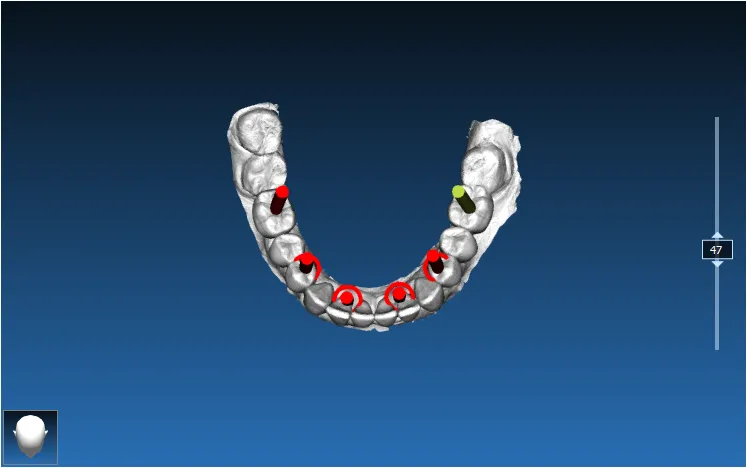

Surgical Guide Design Portfolio

Dental implant guides, apical resection & autotransplant cases from our practice

Dual Arch Rehabilitation — All-on-4 & All-on-6

Complete upper and lower jaw rehabilitation. All-on-4 concept for maxilla and All-on-6 for mandible with custom surgical guides.